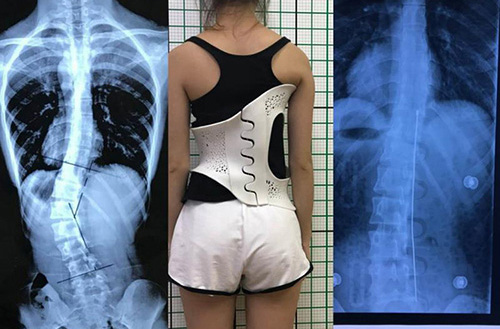

此外,在外固定支具研制方面,3D打印所起到的作用也不容忽视。对于意外摔伤导致骨折的患者来说,适宜的热塑夹板、可卸式泡沫夹板、高分子夹板等外固定支具,有助于帮助患者快速恢复,并降低发生二次骨折的风险。

(3D扫描和3D打印技术辅助制造的个性化脊柱矫正支具)